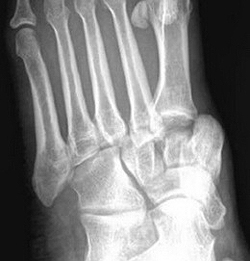

(Слева) При рентгенографии стопы в передне-задней проекции определяется смещение таранной кости кпереди и медиально. Ладьевидная и пяточная кости вместе с остальными костями стопы смещены латерально.

(Справа) У этого же пациента при рентгенографии голеностопного сустава, выполненной в проекции суставной щели, визуализируется латеральное смещение задней суставной поверхности пяточной кости и суставной поверхности ладьевидной кости. Латеральный вывих подтаранного сустава встречается реже, чем медиальный. (Слева) У этого же пациента при КТ в сагиттальной плоскости в коаном режиме, выполненной после неудачной попытки репозиции, определяется импрессионный перелом таранной кости, который возник вследствие ее сдавливания задней суаавной поверхноаью пяточной кости. Этот перелом послужил препятствием для выполнения репозиции.

(Слева) При рентгенографии голеностопного сустава в передне-задней проекции определяется латеральный вывих подтаранного сустава. Латеральное смещение пяточной кости указывает либо на ее вывих, либо на ее перелом. Чтобы отличить вывих от перелома, необходимо выполнить рентгенографию еще и в боковой проекции.

(Справа) У этого же пациента при рентгенографии голеностопного сустава в боковой проекции подтверждается наличие вывиха подтаранного сустава. Задняя суставная поверхность пяточной кости не сочленяется с соответствующей суставной поверхностью таранной кости. Кроме того, выявляется перелом латерального отростка таранной кости. Суставные поверхности таранно-ладьевидного сустава конгруэнтны. (Слева) При рентгенографии голеностопного сустава в передне-задней проекции определяется медиальный вывих подтаранного сустава. Задняя суставная поверхность таранной кости не сочленяется с соответствующей суставной поверхностью пяточной кости.